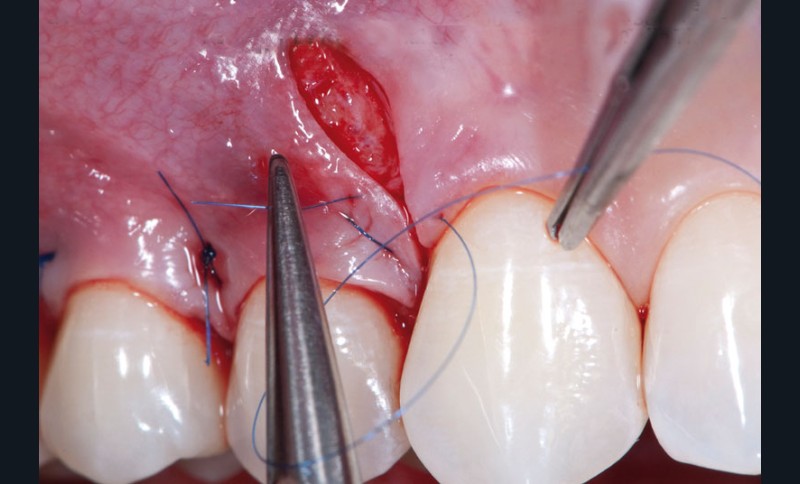

Le concept de microchirurgie a montré un intérêt croissant ces dernières années. Il permet au clinicien de réaliser des interventions chirurgicales très précises et atraumatiques avec des instruments plus petits et des sutures plus fines. Mais, y a-t-il des bénéfices cliniques mesurables ? Les principes de microchirurgie procurent-ils de réels avantages s’ils sont comparés aux concepts conventionnels de chirurgie parodontale ? La conférence du Docteur Zuhr répondra à ces questions et présentera une synthèse des innovations et des évidences scientifiques dans ce domaine.

Jeudi 7 mai : « Appliquer les principes de microchirurgie en parodontologie et en implantologie », conférence du Dr Otto Zuhr

Jeudi 7 mai : « Appliquer les principes de microchirurgie en parodontologie et en implantologie », conférence du Dr Otto Zuhr